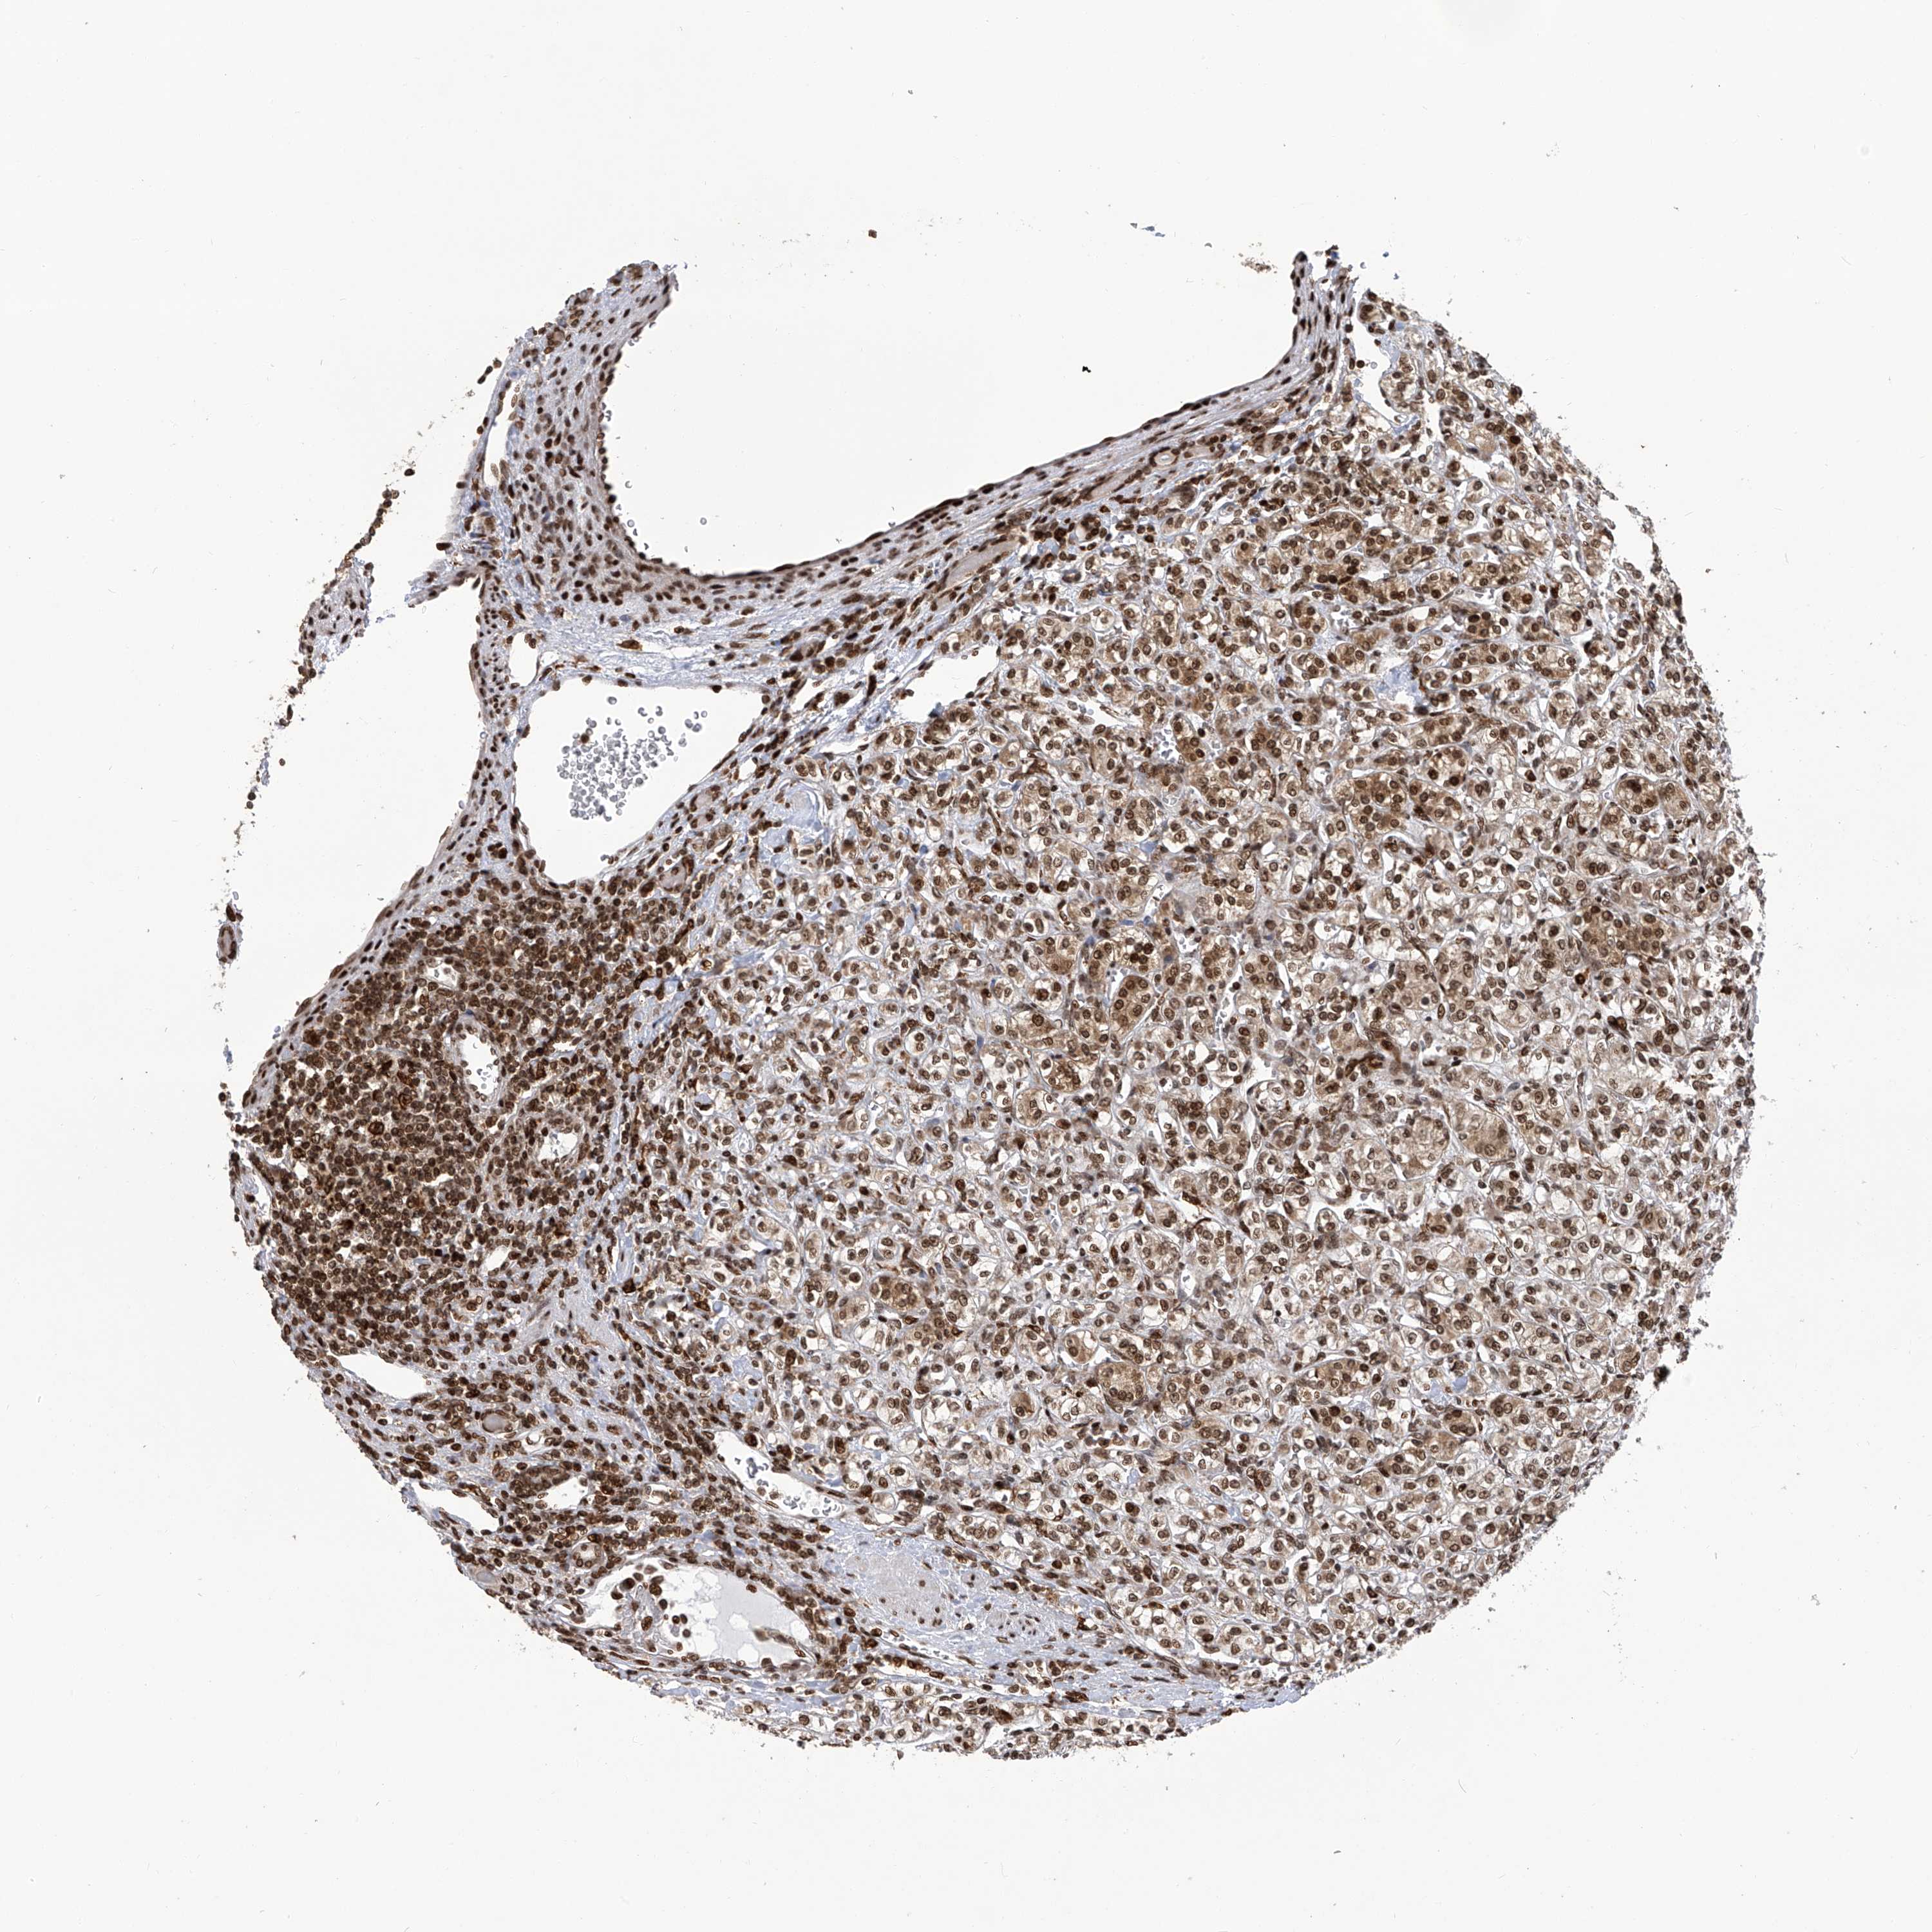

CANCER RENAL CANCER Show tissue menu

KICH TCGA KIRC TCGA KIRC VALIDATION KIRP TCGA PROTEIN RCC CPTAC PROTEIN EXPRESSION

KIDNEY CHROMOPHOBE (TCGA) - Interactive survival scatter ploti

PAK1IP1 is potential prognostic, high expression is unfavorable in Kidney Chromophobe (TCGA)